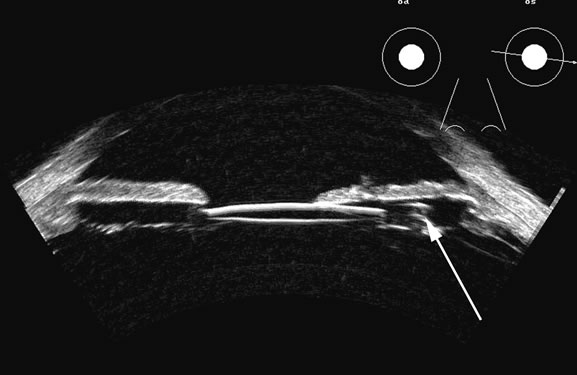

Fresh blood in the vitreous may be acoustically clear since the red cells may not have congealed sufficiently to form a good echo-producing surface.8 A retracted “hyaloid” or posterior limiting membrane (PLM) of the vitreous can be shown with most B-scan instruments, but paradoxically a retracted vitreous may not be seen as well with higher-resolution, more highly focused transducers because they display less area of the reflective surface. Blood collected on the surface of the PLM enhances this surface and may, in some cases, make the PLM resemble a detached retina, since its anatomic dimensions can be similar to the retina. Three differences may help distinguish the two structures. First, kinetic scanning reveals a lack of attachment at the optic nerve for a PLM. Second, the PLM is irregular in reflection and thickness (usually thicker than the retina) between the ora and the disc, and usually the surface cannot be traced forward to the ora on the B-scan display. Third, the amplitude of the echoes from the PLM is lower than from the retina, except when directly perpendicular to the beam, where they may be similar in amplitude. Many of these features of a PLM are demonstrated in Figure 7, whereas Figure 8 shows a typical detached retina.

Fig. 7. This B-scan ultrasonogram demonstrates retinitis proliferans with typical vitreous membrane attaching to the proliferative membrane (arrows) that can resemble a traction detachment. Scanning at right angles helps distinguish proliferative membranes from retinal traction membranes, as they have less reflectivity than retina.

Fig. 8. A retinal detachment (arrow) is very easily detected as a high-amplitude, usually relatively rigid or gently wafting structure connecting always to the optic nerve head in a complete detachment, and usually traceable anterior to the ora serrata. Variations of this pattern can be seen, depending on the plane of the cut and the extent of the detachment, but the height of the echo on A-scan should always be maximal in order to differentiate retina from other, similar membrane formations.